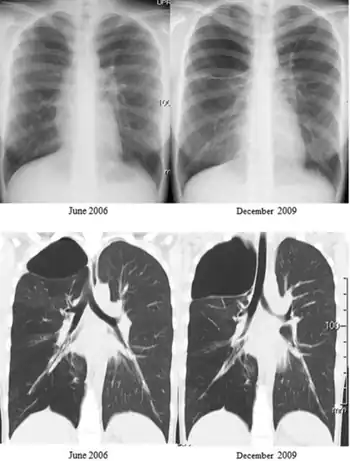

Swyer–James syndrome is a manifestation of postinfectious obliterative bronchiolitis.[2] In SJS, the involved lung or portion of the lung does not grow normally and is slightly smaller than the opposite lung.[3] The characteristic radiographic appearance is that of pulmonary hyperlucency, caused by overdistention of the alveoli in conjunction with diminished arterial flow.[4][5] and has been linked to adenovirus type 21, a type of adenovirus infection.[6]

In appearance Swyer–James normally leaves shadowing in a CT scan in the upper lobar regions of one or (rarely) both lungs. People with the illness operate in much the same way as patients with mild bronchiectasis. As a result, the illness can go undiagnosed for some time. With current pharmaceutical developments, the prognosis is good for sufferers of the illness to lead normal and healthy lives.